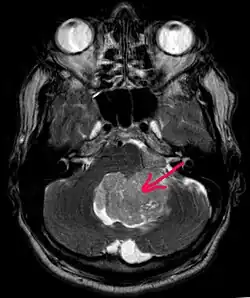

В типичных случаях на МРТ эпендимомы видны в виде объёмных образований, которые заполняют, а иногда и полностью тампонируют полость IV желудочка и распространяются в большую затылочную цистерну или боковую цистерну моста. Солидная часть новообразования на Т1-взвешенных томограммах выглядит изо- или даже гипоинтенсивной и гиперинтенсивной на Т2-взвешенных томограммах[24].

Дифференциальная диагностика эпендимом с другими глиомами основывается в основном на их локализации и топографии, а не на различиях интенсивности сигнала или степени контрастного усиления[25]. Кистозный компонент имеет гипоинтенсивный сигнал на Т1-взвешенных МРТ и гиперинтенсивный по отношению к мозгу на изображениях, взвешенных по Т2. Гетерогенность структуры опухоли обусловлена наличием кист, петрификатов, опухолевой сосудистой сети. После введения контраста отмечается негомогенное усиление средней интенсивности[26]. Дифференциальную диагностику эпендимом боковых желудочков необходимо проводить с медуллобластомами и астроцитомами[23].

Анапластические эпендимомы отличаются более выраженной гетерогенностью сигнала, нечёткостью границ, большим распространением, интенсивным накоплением контраста и наличием зон некроза[24].